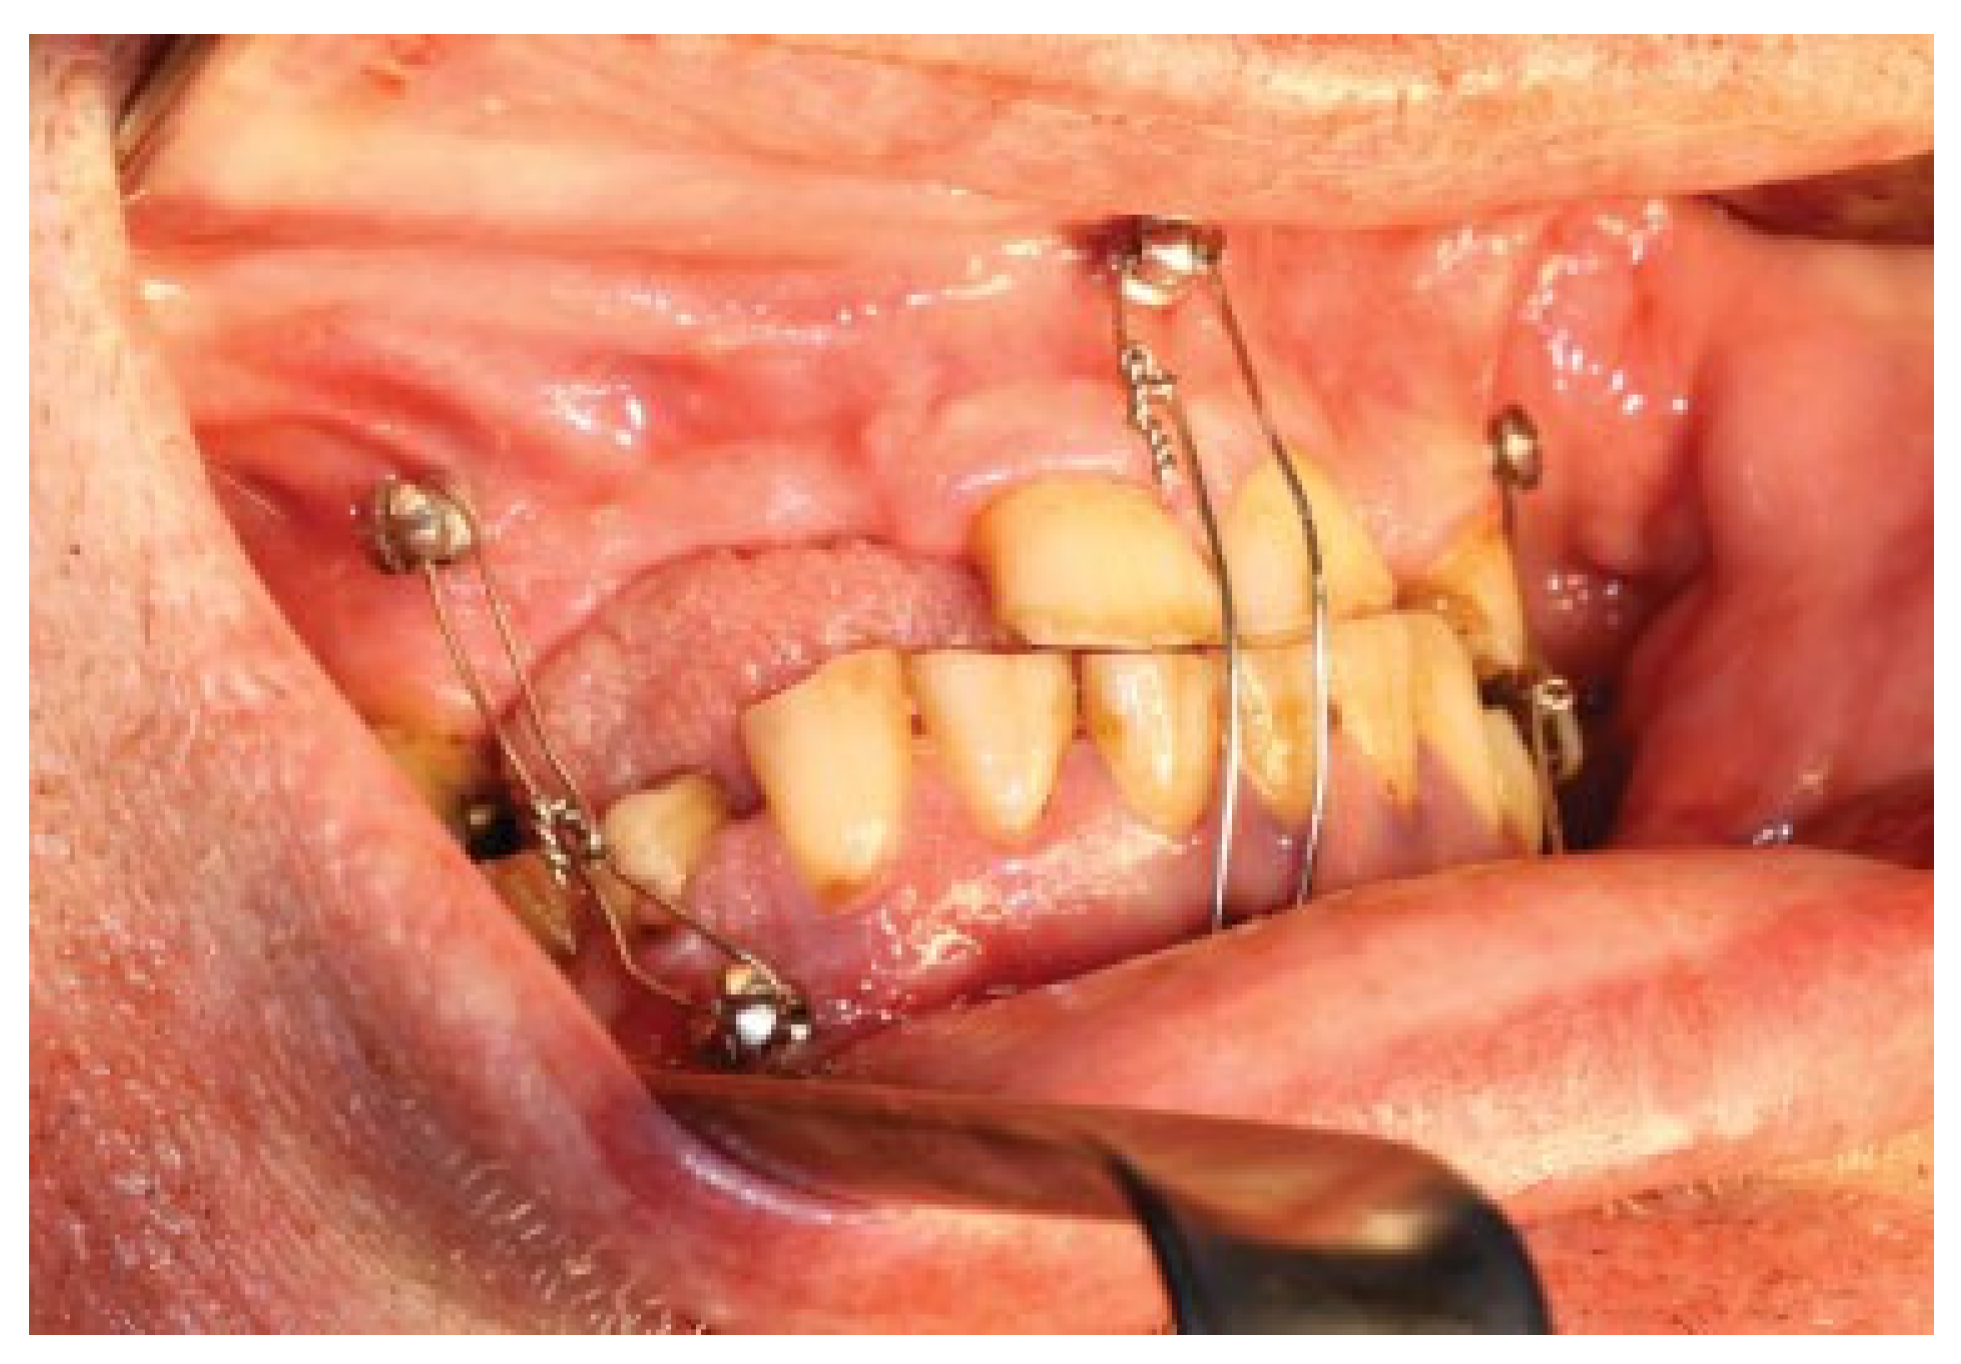

A 57-year-old man sustained a bilateral mandibular body comminute fracture due to a horse-kick trauma to his lower jaw. The subject was obese but otherwise healthy and due to the trauma omitted to the Uppsala University Hospital, Department of Oral & Maxillofacial Surgery. The anterior part of the mandible was severely displaced with a clinical open bite and the subject was taken from the Intensive care unit (ICU) to the Operating room (OR) after one night of monitoring. Partial edentulism was seen in both jaws (Figure 1). Open reduction and fixation of the fractures were performed via an intra-oral route. Noticeable was the difficulty in using a trocar due to the subjects’ constitution with abundance of soft tissue. Two mandibular plates were placed on each side and post-operative situation was evaluated with cone beam computed tomography (CBCT) (Figure 2). Initial healing was uneventful and the patient was not held in maxillo-mandibular fixation (MMF). At the two-week follow-up intraoral fistulas were found in the area of fractures and instability of the osteosynthesis occurred with opening of the bite as a result. The subject was scheduled for secondary surgery and meanwhile oral antibiotics (phenoxymethyl penicillin and metronidazole) were prescribed.

Figure 1.

Preoperative situation. Displaced bilateral mandibular body fracture after trauma by a horse-kick.